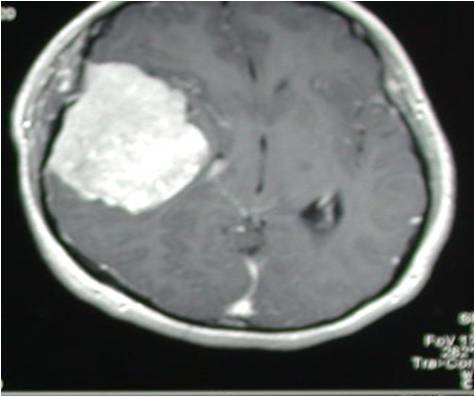

巨大中颅底脑膜瘤切除术

术后MRI